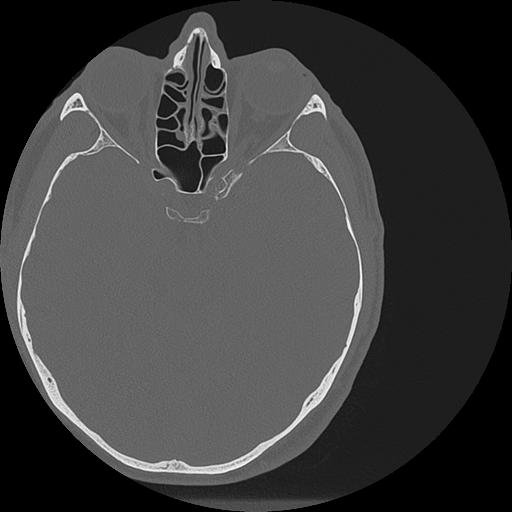

7 HUESO,,Vol,0.5,HUESO,,